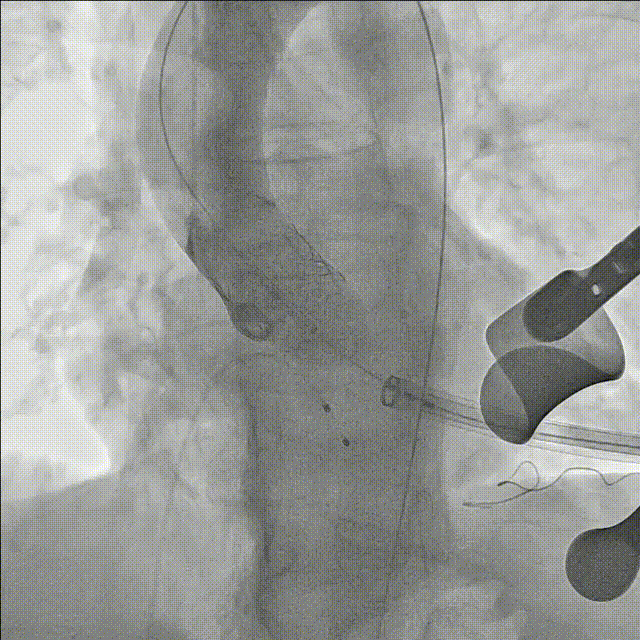

瓣膜定位后,心脏起搏至180bpm,血压下降后,在主动脉根部造影的同时迅速充盈球囊,释放瓣膜

瓣膜释放